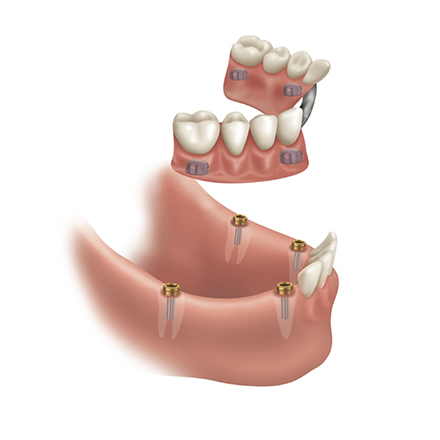

- Implant “Snap-In” Overdentures: Dentures that securely “snap” into 2–4 implants for ultimate confidence and stability.

- Implant-Retained Partial Dentures: Keep your remaining healthy teeth by using implants to anchor partial, removable dentures for extra security without visible metal.